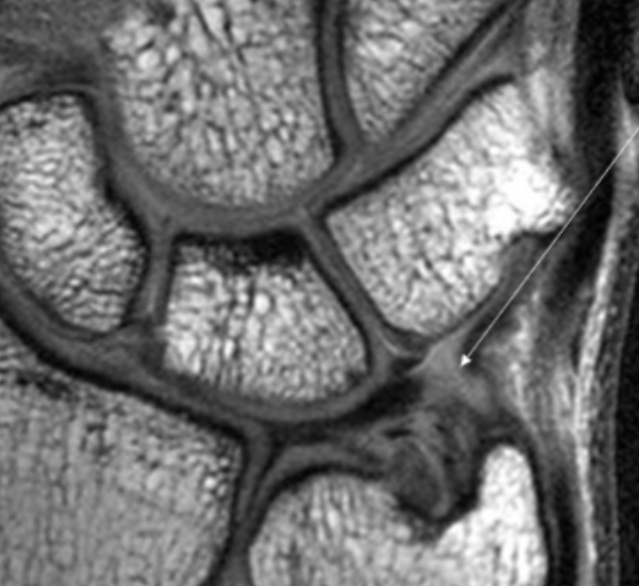

Describe the pathology indicated by the arrow (Cor PD).

Scapholunate ligament tear